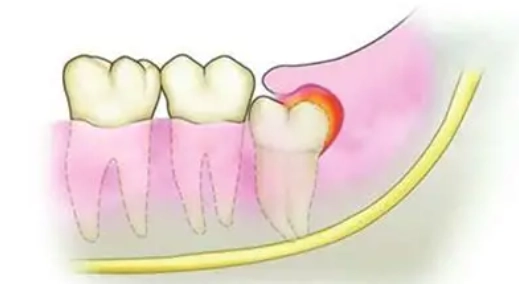

| 1. 智齒冠周炎 | 腫脹集中在最後一顆牙(智齒)的牙齦瓣上,可能覆蓋部分牙冠。按壓有膿或血水滲出,伴隨劇烈抽痛、張口困難。 | 20-35歲年輕族群最常見。飯後食物殘渣卡進智齒與牙齦的縫隙,清潔不到而引發感染。 | 高(易惡化) |

- 腫脹的位置是不是就在最後一顆冒出來的牙齒(智齒)周圍? → 指向智齒冠周炎。

- 智齒冠周炎: 先做「冠周沖洗」上藥,消炎後評估是否需拔除智齒。你可以參考台灣衛福部國健署的口腔健康資訊,了解智齒照護的重要性。